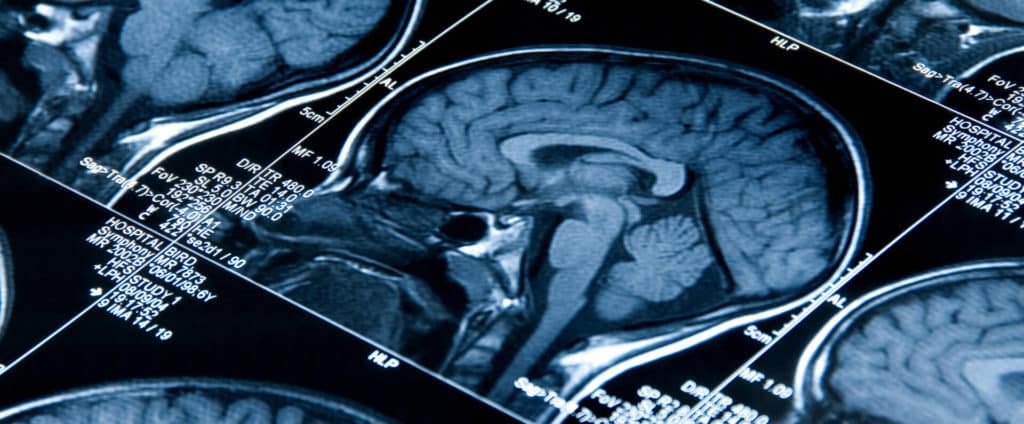

Blunt Force Trauma to the Head

Seeking Compensation for a Blunt Force Injury Blunt force trauma to the head, a common injury in accidents and assaults, can lead to severe physical and psychological effects. Victims may face long-term health difficulties, financial strain from medical bills, and potential loss of income due to disability. In such instances,